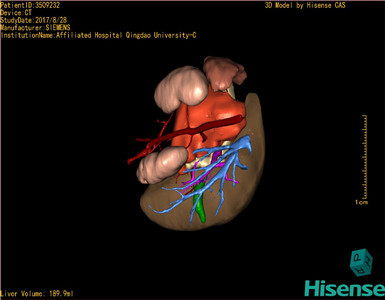

CT结果输入海信CAS系统后行3D重建及手术规划后,于2017-8-29全麻下行“腹膜后畸胎瘤切除术+肠系膜上动脉吻合术”手术治疗:

术前三维重建及手术方案设计:

将0.625mm双源薄层CT资料的静脉期和动脉期Dicom格式文件导入海信CAS系统。

通过调节窗宽窗位调整CT序号,对肿瘤,肝实质,胆囊,下腔静脉,肿瘤,肝动脉、门静脉及肝静脉等进行三维重建;系统自动计算肿瘤体积和肝脏体积。

模拟手术操作,自动计算切除肿瘤体积。肝脏体积为453.7ml,通过比对2-3岁正常肝脏体积为475.97±99.7ml,通过术前模拟手术,精准判断切除后剩余肝脏体积能耐受,避免肝衰竭发生。

术前三维重建:

重建图片